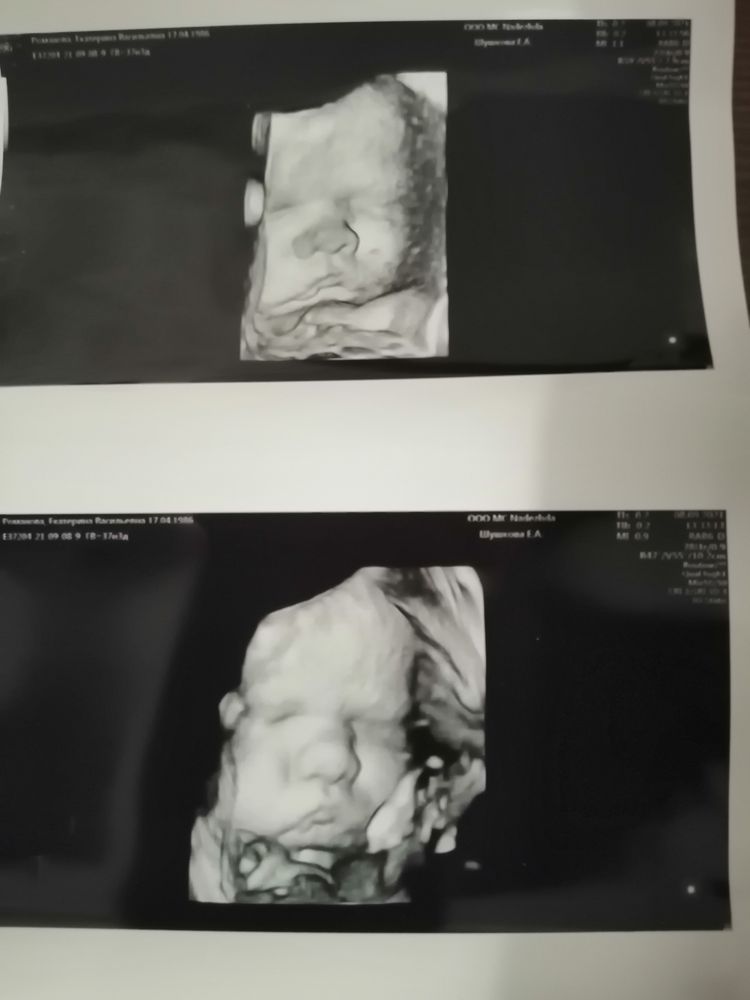

Последнее узи в 38 недель

Это вы в платную ходили? Как хорошо фото получилось! Я узнавала, сказали на этих сроках не гарантируют фото ребёнка хорошее, тк крупный уже.

Чудесно ведь что кровотоки в норме 👌Какой хорошенький щекастик😍 тебе похож на Антошку? Мне так по фото которые видела ваши-да )))

Серьезный мужчина какой ☺ Лёгких родов!)